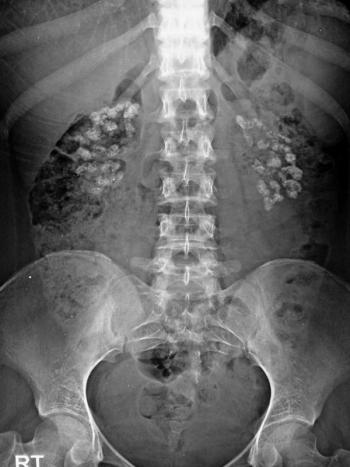

Middle age female with back pain and left sided radiculopathy. What most likely represents the imaging finding?